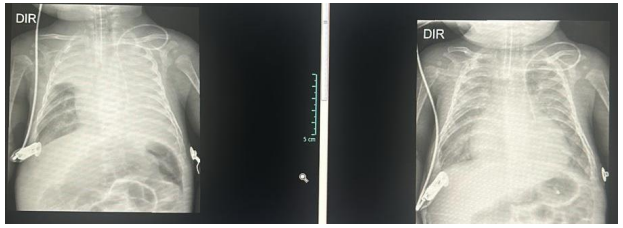

Seguem as imagens referentes ao momento imediatamente posterior à intubação e 6 horas após o início da ventilação mecânica.

Diante do caso, qual complicação o paciente apresentou, sua conduta e materiais utilizados?